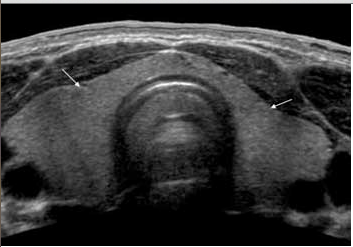

Pics form ultrasound-images.com :

PAPILLARY CARCINOMAthyroid_papillary carcinoma